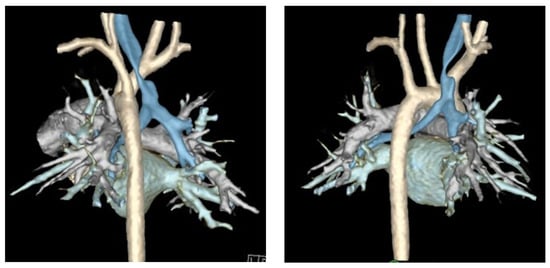

Background: Tracheobronchial disease, including tracheomalacia (TM) and tracheobronchomalacia (TBM), is a spectrum of congenital and acquired airway disorders characterized by the collapse of the tracheal or mainstem bronchial walls during expiration, particularly when there are increased intrathoracic pressures. Traditional surgical approaches to treat [...] Read more.

Background: Tracheobronchial disease, including tracheomalacia (TM) and tracheobronchomalacia (TBM), is a spectrum of congenital and acquired airway disorders characterized by the collapse of the tracheal or mainstem bronchial walls during expiration, particularly when there are increased intrathoracic pressures. Traditional surgical approaches to treat severe medically refractory TM include anterior approaches, such as aortopexy or anterior tracheopexy. Recently, posterior tracheopexy has emerged to address the widened and mobile posterior tracheal membrane which can cause transient airway obstruction. Method: The National Institute of Health, National Library of Medicine, PubMed, and MEDLINE databases were queried for manuscripts related to posterior tracheopexy in the pediatric population. Preoperative diagnostics, anesthetic considerations, operative technique, clinical outcomes, and operative complications were analyzed in each manuscript. Results: Patients with severe medically refractory cases of TM who are being considered for posterior tracheopexy should undergo thorough preoperative workup by a multidisciplinary team. Cross-sectional, dynamic thoracic imaging and a “quadruple endoscopy”, incorporating laryngoscopy, dynamic bronchoscopy, distal bronchoscopy, and esophagogastroduodenoscopy (EGD) should be obtained as part of a standardized preoperative assessment. Posterior tracheopexy for pre-existing TM significantly improves respiratory symptoms, respiratory infection rates, brief resolved unexplained events, and ventilatory dependence. Recently, posterior tracheopexy during TEF/EA repair has been described and aims to reduce the risk of patients developing TM, the risk of TEF recurrence, and respiratory morbidity following TEF/EA repair. An ongoing randomized controlled trial may help to elucidate the efficacy of primary posterior tracheopexy in select neonates with TEF/EA. Conclusions: Posterior tracheopexy is a valuable surgical technique for the treatment of TM or the reduction in respiratory morbidity following TEF/EA repair in select neonates. Full article

Figure 1